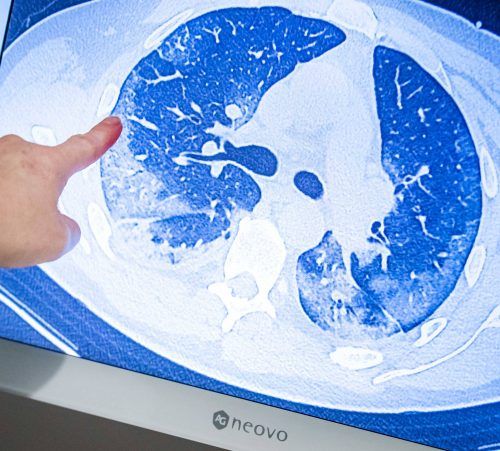

Bleibende Lungenschäden durch Covid-19?

Kann eine Infektion mit dem Virus Sars-CoV-2 zu Spätschäden an der Lunge führen? Noch gibt es auf diese Frage keine klare Antwort. Doch: Es mehren sich Berichte, die darauf hindeuten.